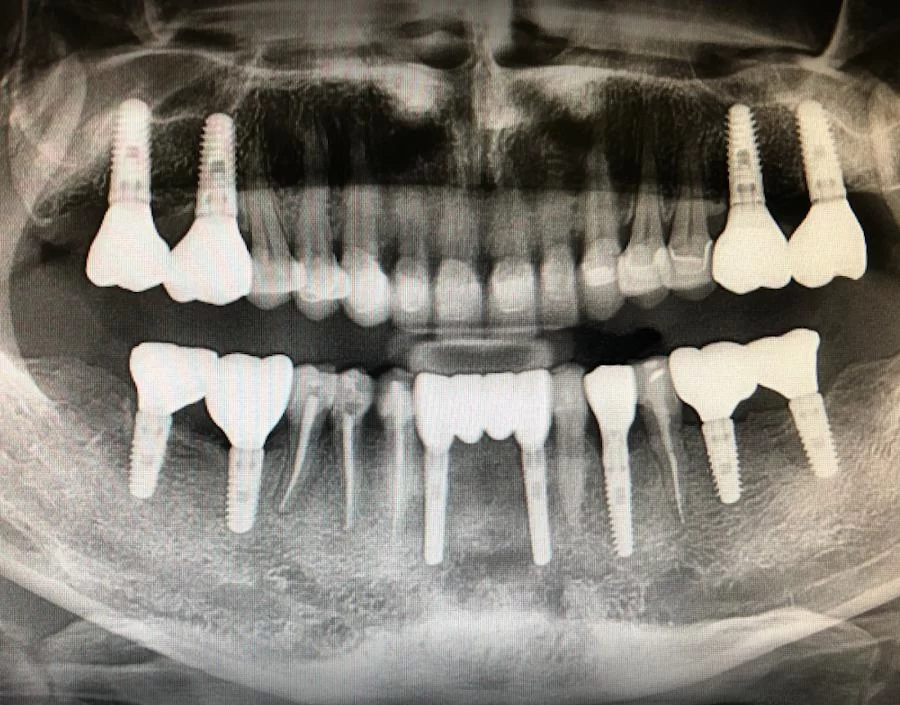

Dr. Ramsey Amin is a board-certified dental implant specialist with over 22 years of experience. His practice focuses exclusively on implant dentistry, offering a range of implant solutions from single tooth replacements to full mouth reconstructions. He is a Diplomate of the American Board of Oral Implantology/Implant Dentistry and a Fellow of the AAID. He is an officer in the AAID Western District and serves on the AAID Education Committee. Dr. Ramsey Amin is part of the implant editorial board for “Dentistry Today.”

- Full Mouth Dental Implants: This option is for patients who are missing most or all of their teeth. It involves placing multiple implants to support a full set of dentures or a fixed bridge.

- Multiple Dental Implants: This is for patients missing several teeth. Individual implants are placed for each missing tooth, providing a stable and natural-looking solution.

- Single Tooth Dental Implants: This is for patients missing only one tooth. A single implant is placed to support a crown, restoring the missing tooth without affecting adjacent teeth.

- Extensive Experience: With over 22 years of experience and having placed more than 10,000 dental implants, Dr. Amin is highly skilled in all aspects of implant dentistry.